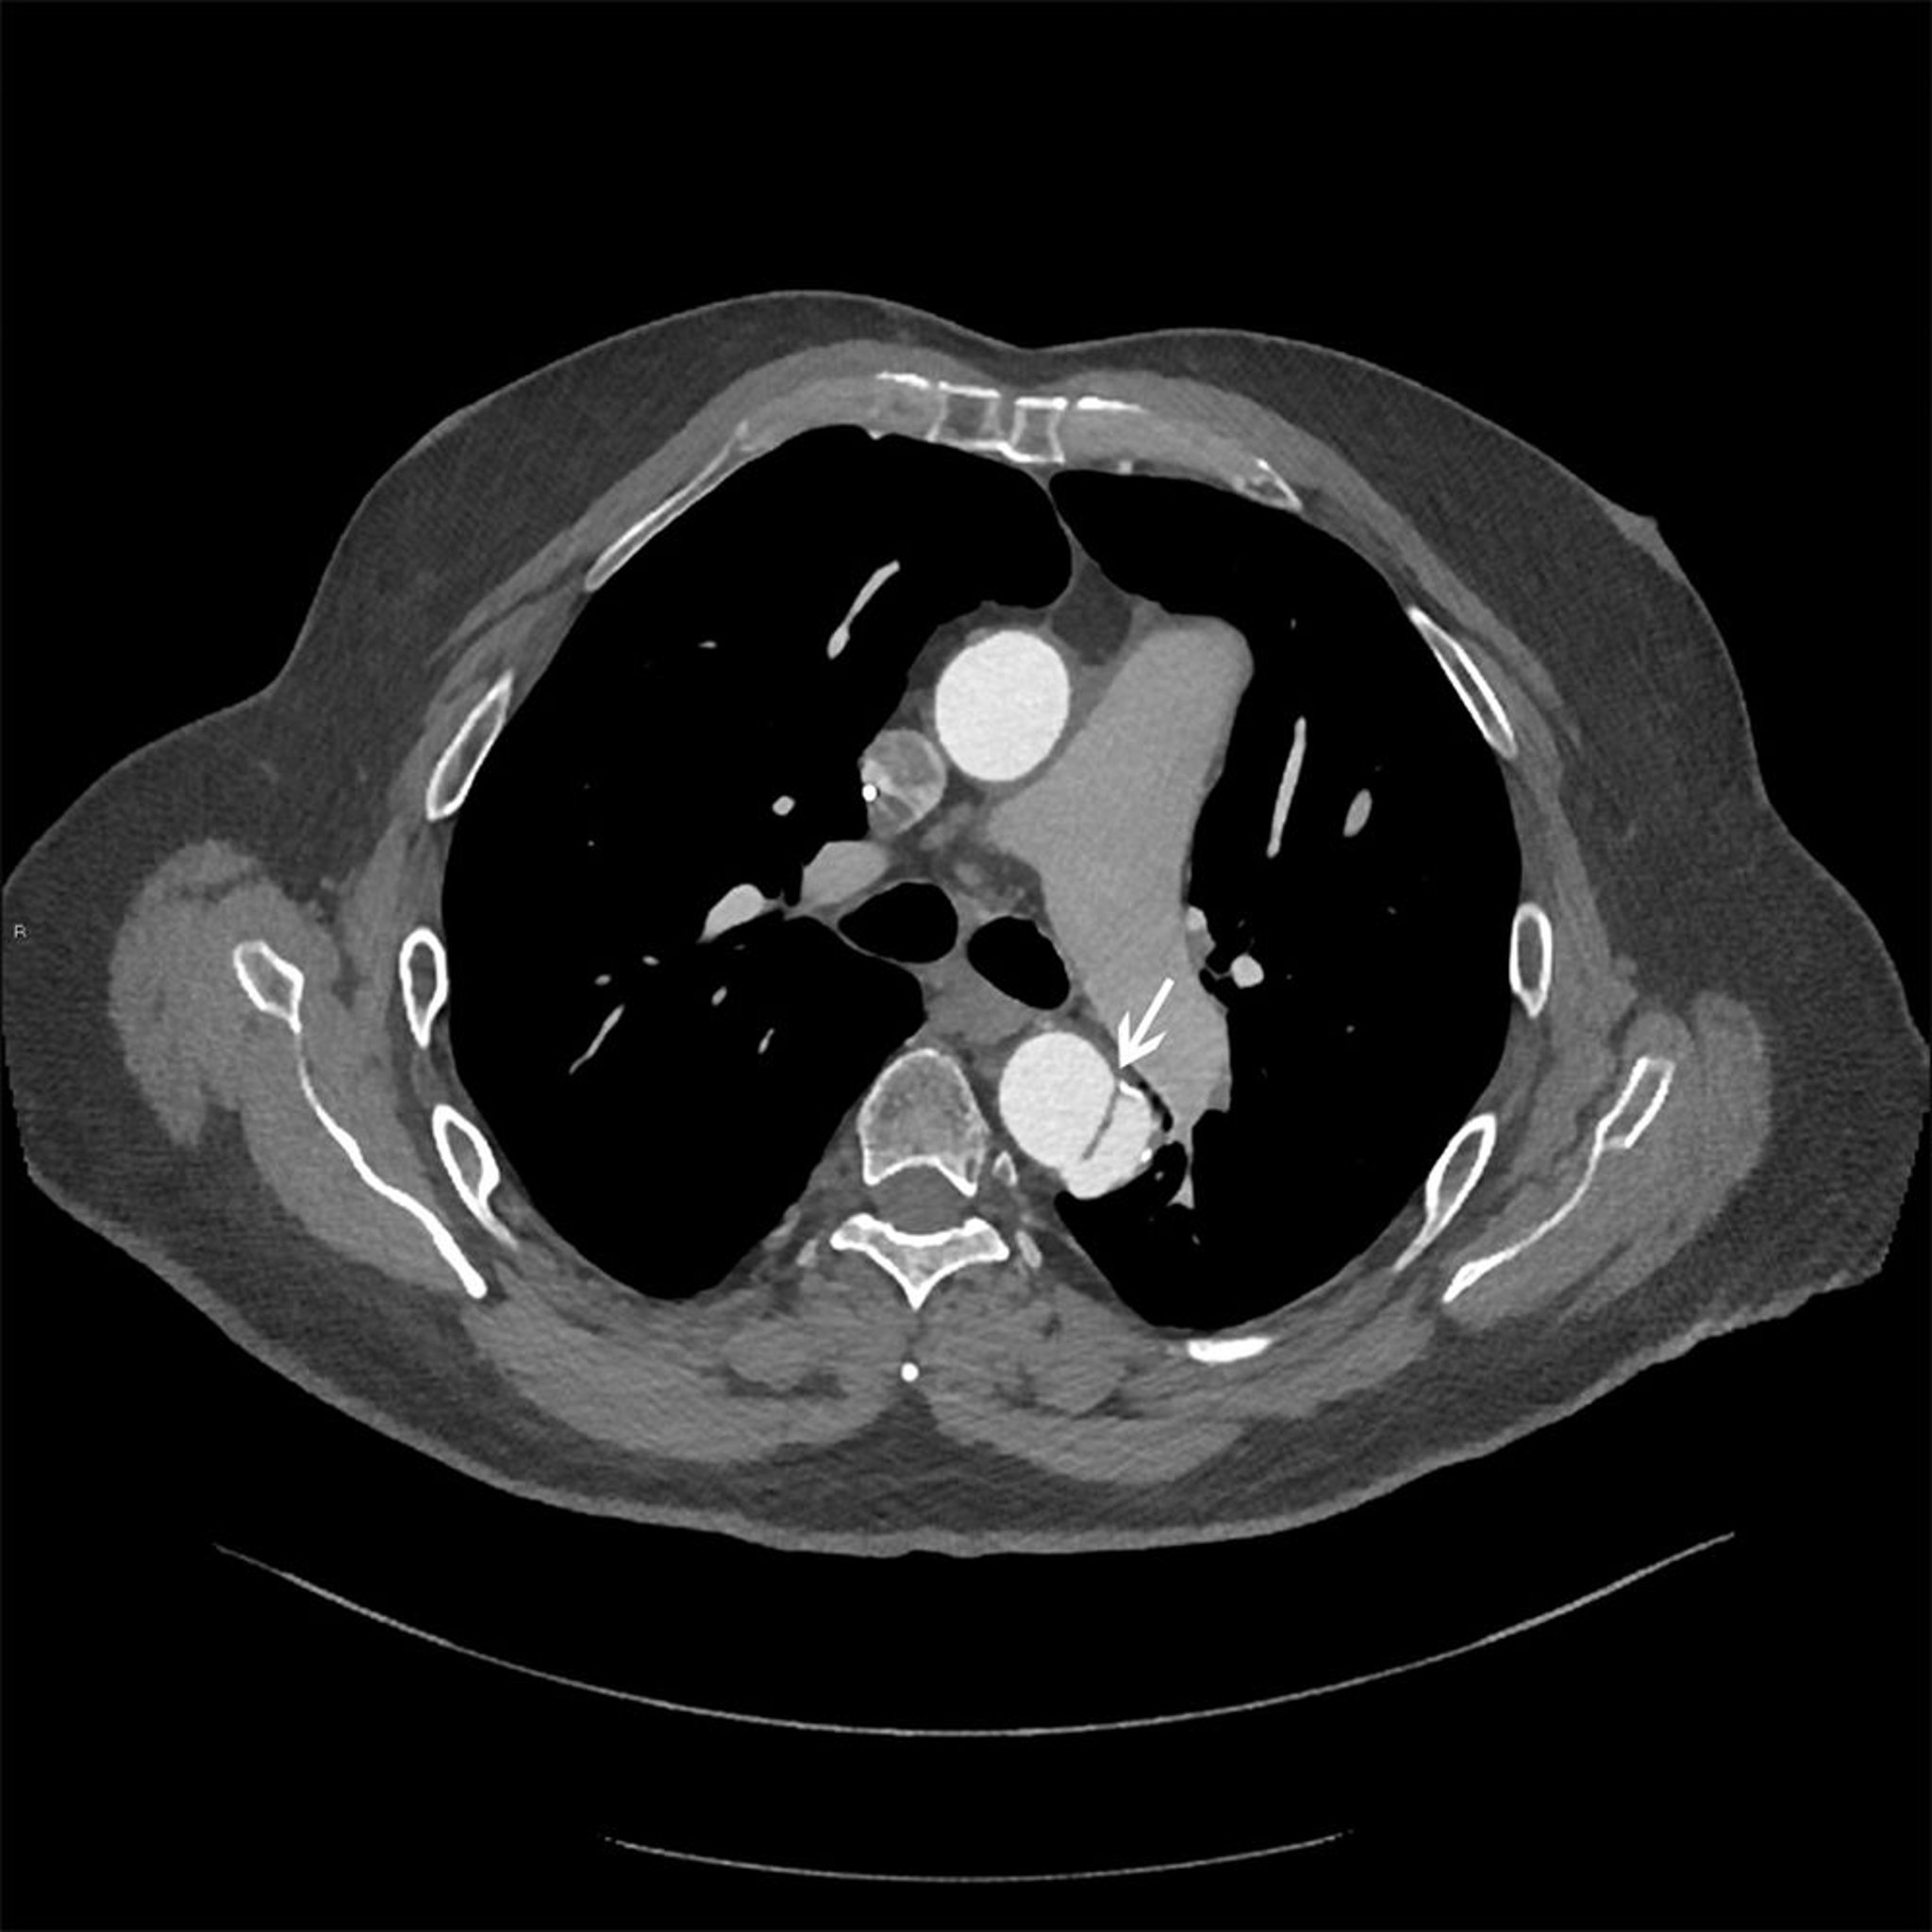

Dissezione dell'aorta toracica (classificazione di Stanford di tipo B)

Immagine assiale del lembo di dissezione (freccia bianca) nell'aorta discendente del torace.